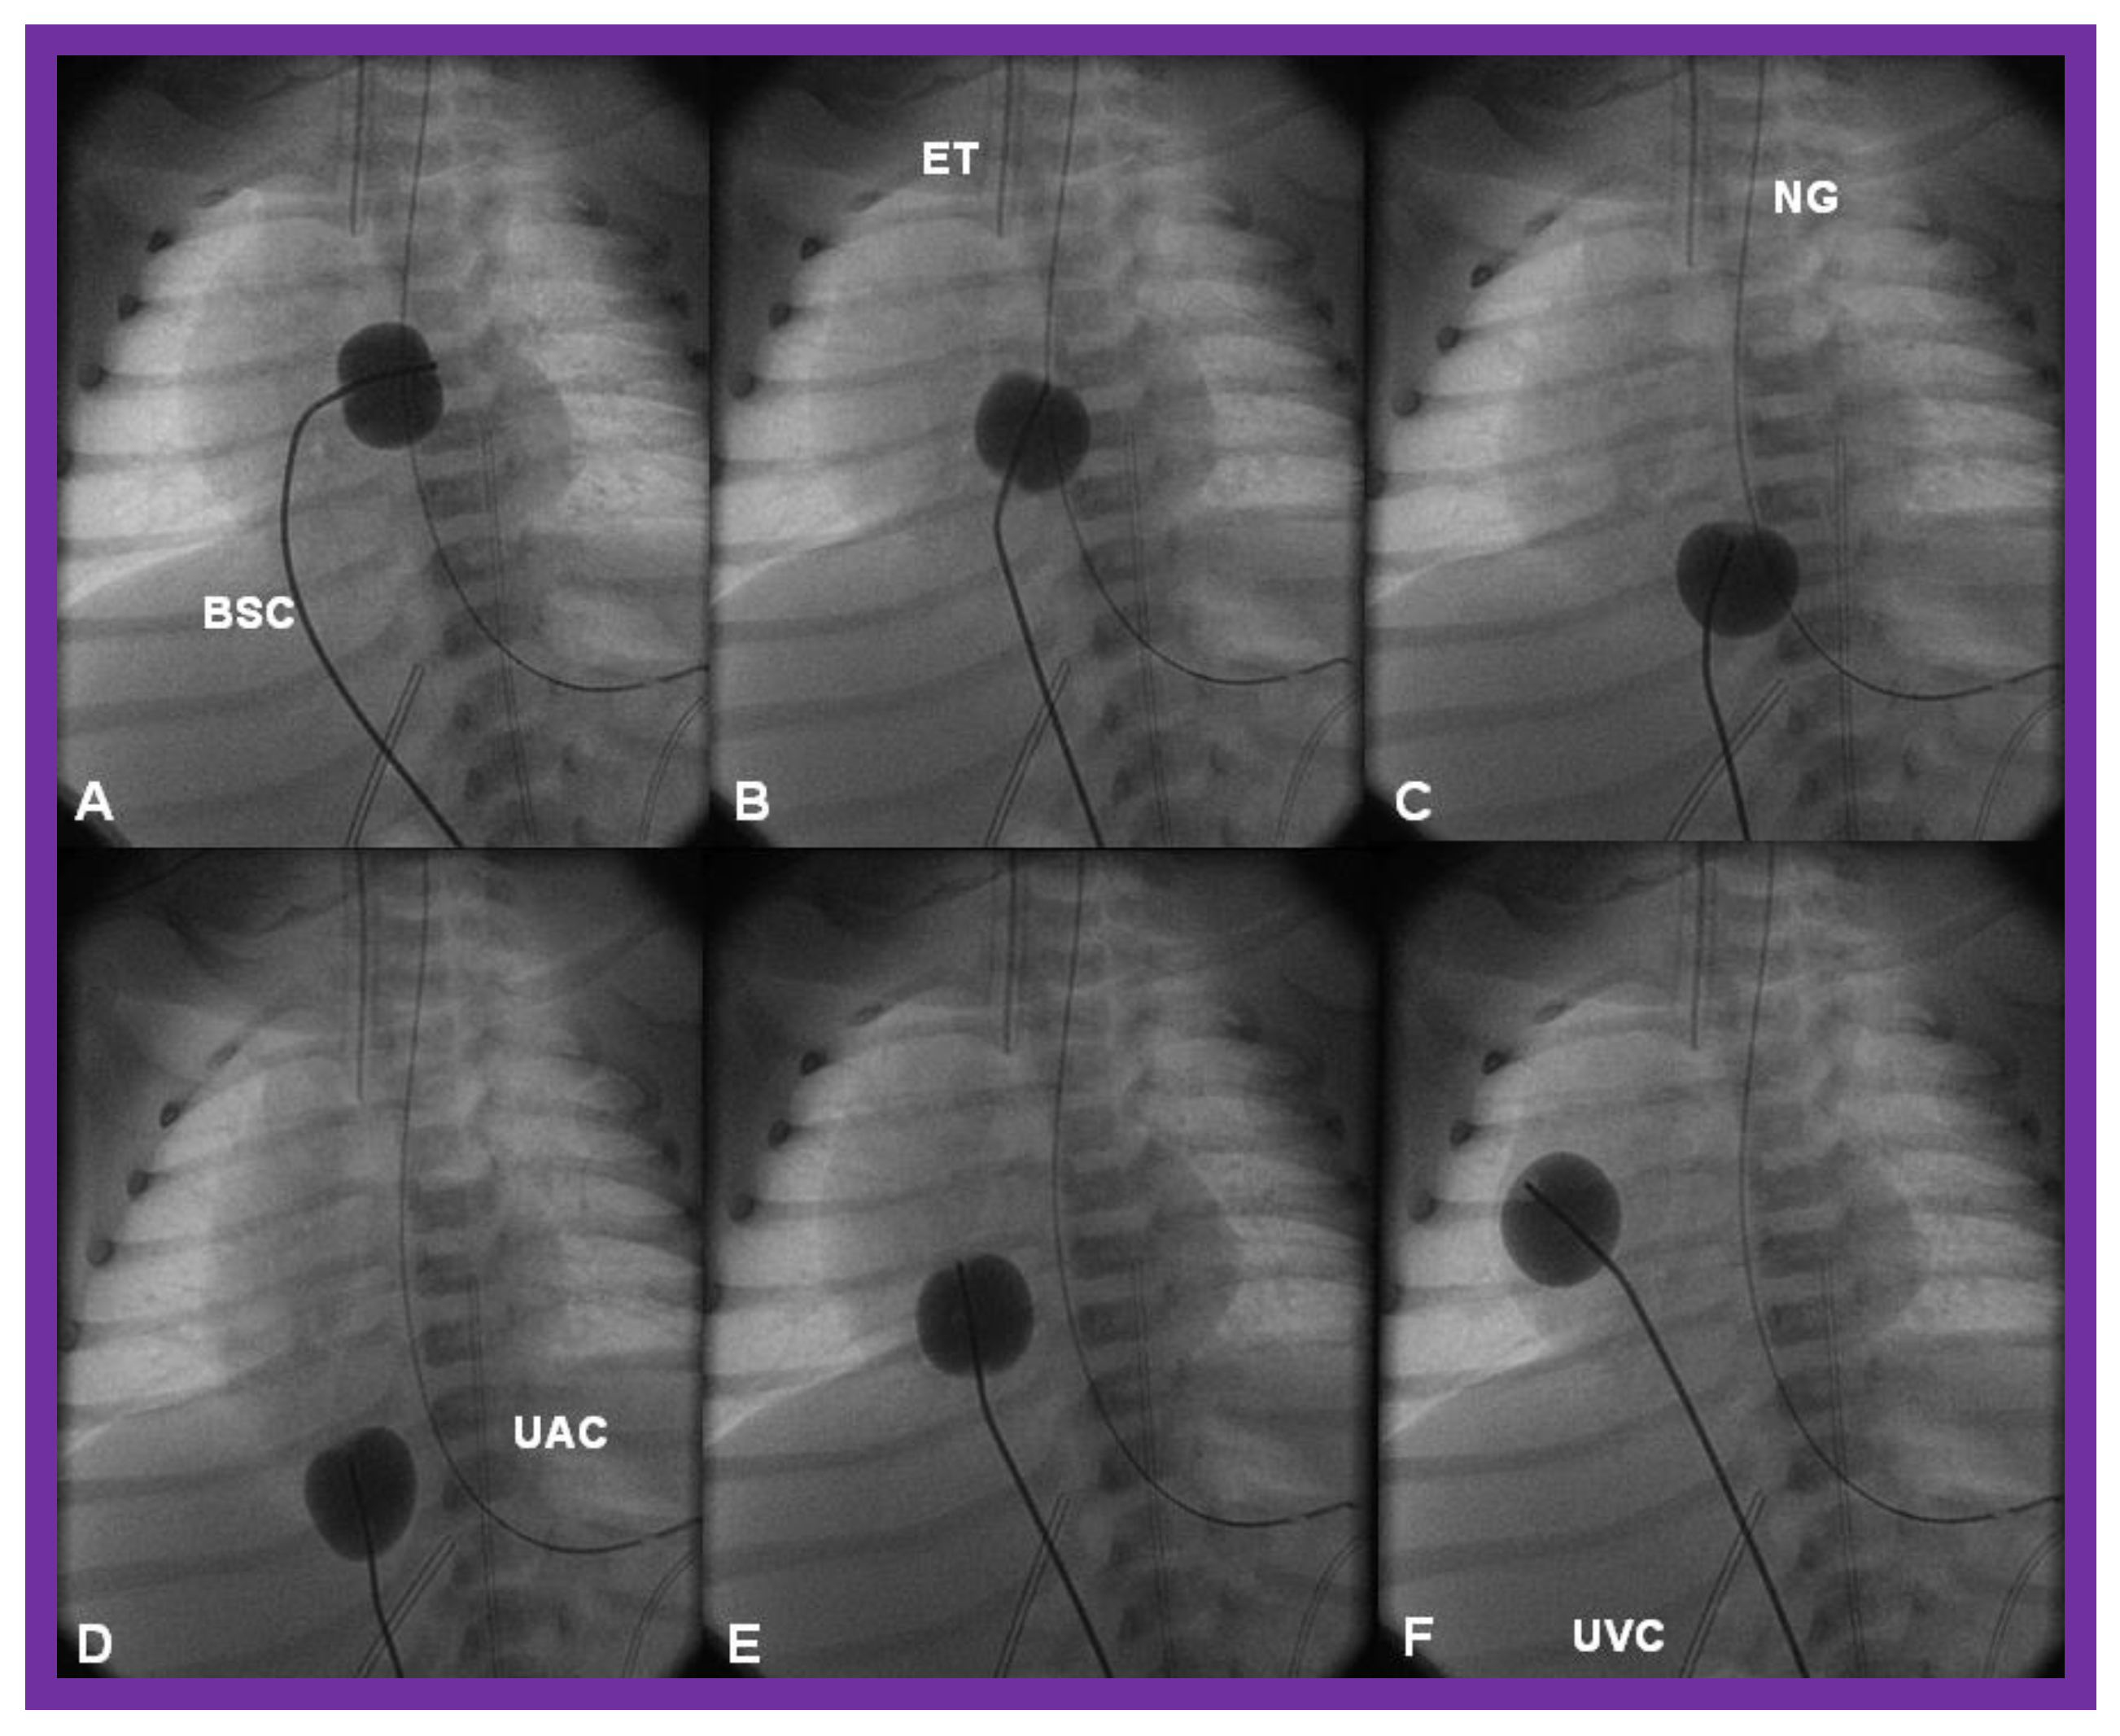

Figure 12.

Cinfluroscopic frames demonstrating the procedure of Rashkind’s balloon septostomy. Initially the balloon is inflated in the left atrium (A). The balloon septostomy catheter (BSC) is rapidly and forcefully pulled into the right atrium (B) and inferior vena cava (C,D) and quickly advanced back into the right atrium (E,F). The entire procedure is done as one single motion. Rapid advancement of the BSC into the right atrium (E,F) is done in order to avoid inadvertent occlusion of the inferior vena cava if failure to deflate the balloon occurs (this is quite rare). At about the same time the balloon is deflated. ET, endotracheal tube; NG, nasogastric tube; UAC, umbilical arterial catheter; UVC, umbilical venous catheter.